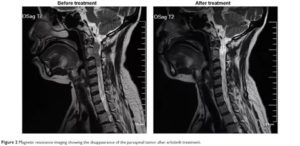

- Для выявления неврологии МРТ является лучшим вариантом обследования. Магниторезонансная томография показывает не только аномалии позвонков и межпозвоночных образований, она также нужна для исследования нервных стволов и расположенных в области позвоночника сосудов;

- Магнитно-резонансная томография (МРТ);